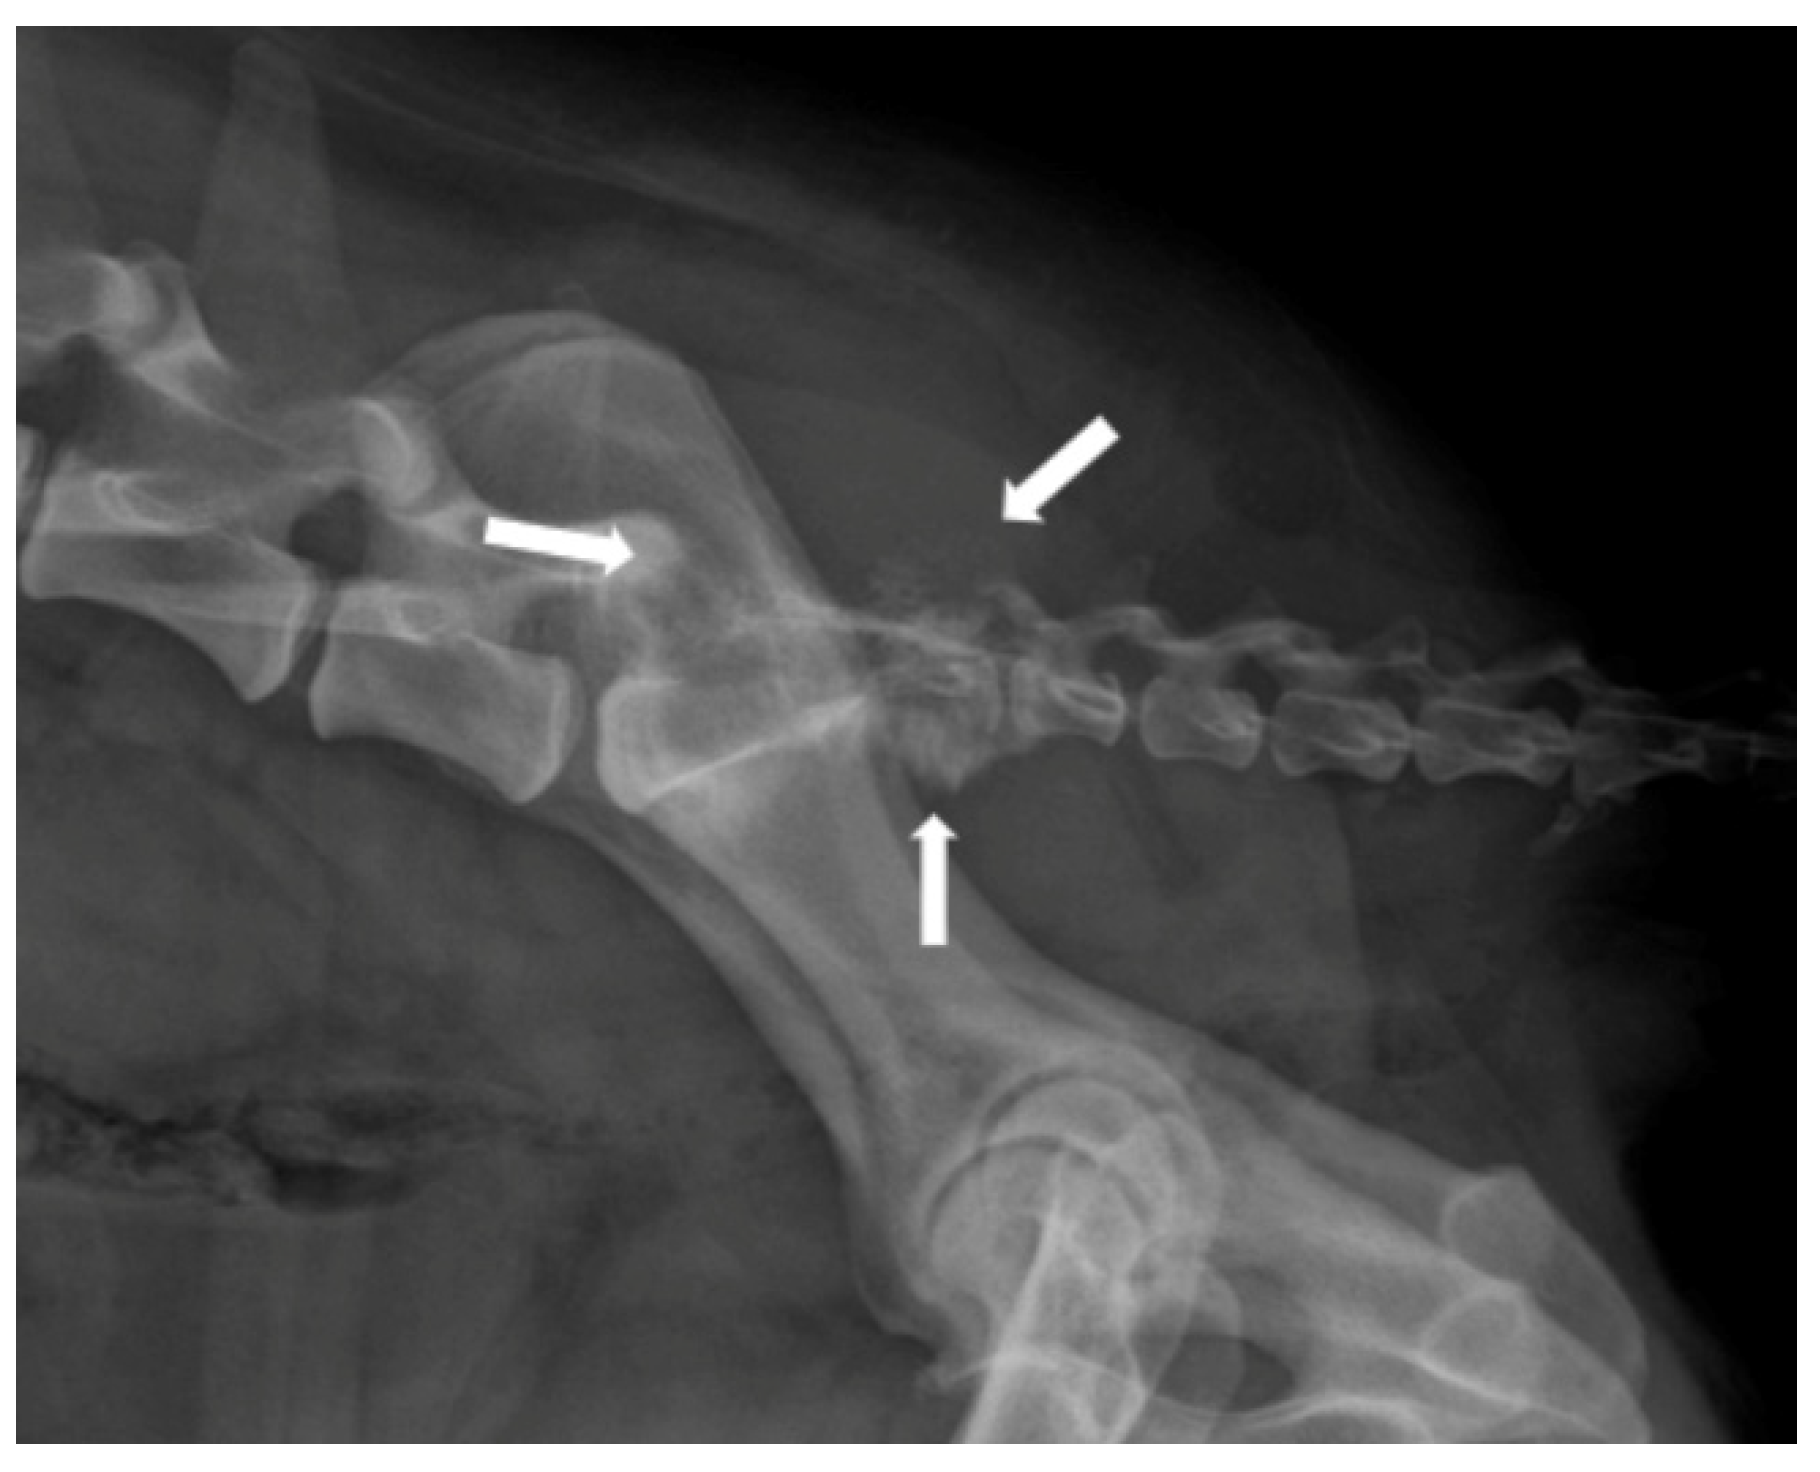

3.2. Degenerative Myelopathy